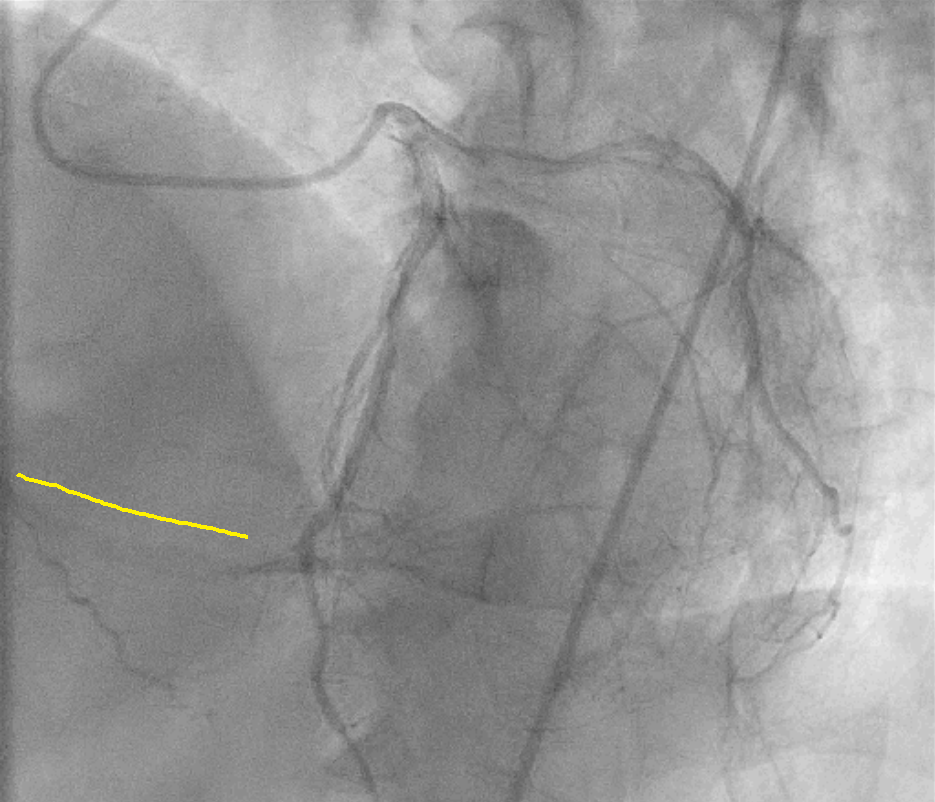

Angiogram suggestive of patent stents in LAD and LCX; and dominant right coronary artery with proximal cut off along with tram track calcification. The RCA is filling distally by retrograde collaterals Rentrop III.

7F Femoralapproach and AL 0.75 was taken. Lesion crossed with Runthrough wire with fine cross support. Predicated with 1.5*5mm semicomplaint balloon , could not crossed and busted distally. ROTA 1.5mmburr, couldn't crossed at mid RCA, even at 200000 rpm speed, likely wire bias. ROTA 1.25mm burr crossed at 150000 rpm and after that, lesion was predilated with 2.5*15 mm semicomplaint balloon, and 2.75*15 mm non complaint balloon. Stent 2.5*38mm was deployed in distal-mid RCA at 12 atm, and proximal stent 3*32 mm was deployed in mid-proximal RCA at nominal pressure with Guidezilla support.Post stent dilation was done distally with 3*15 mm and proximally with 3.5x15mm Non-complaint balloon @ 16-18 atm. Good end result.